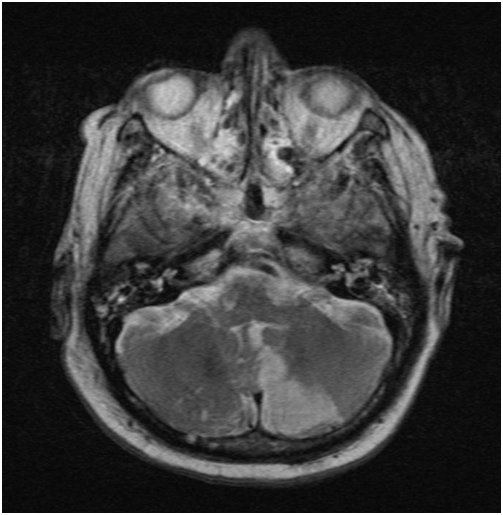

After surgery a slurred speech and a deviation of the eyes were observed. The MRI (1,5 T, T1w SE sagittal, FLAIR coronar, T2w TSE transversal, bleeding- and diffusions sensitive sequences T2w TSE sagittal TOF angiography and secondary multiplanar reconstructions) showed multiple ischemic regions in the dorsal flow area of the cerebellum on both sides, especially in the pica flow area, the left thalamus, left temporal and occipital due to multiple embolisms (Figure 3). Space occupying cerebral edema was not found.

Figure 3 Cerebral magnetic resonance imaging. The diffusion sensitive sequences (T2w TSE) show a left sided ischemia of the cerebellum following surgery.

Transthoracic echo-cardiography was performed without pathology. Transesophageal echo-cardiography showed a persistent foramen ovale (pfo) with free flow even without Valsalva maneuver. No intracardial thrombi or a major sclerosis of the aorta could be found. Duplex sonography ruled out deep vein thrombosis or pathological flow in the carotids. CT-scans of thorax and cranial MR-angiography excluded pulmonary embolism as well as cerebrovascular diseases, especially of the basilar artery.

A follow-up CT-scan of the brain was performed 6days after surgery. The ischemia right parietal, in the left thalamus and in the left cerebellum marked clearly. At this time the patient was stable on ward and his neurologic deficits reduced significantly under intensive ergo- and physiotherapy. After two years, the patient returned to our outpatient department after a fall; the hip was stable and no residual neurologic deficits were observed. Upon control three and a half years after the embolism the patient showed no signs of neurologic sequelae and no loosening of the implant (Figure 1).